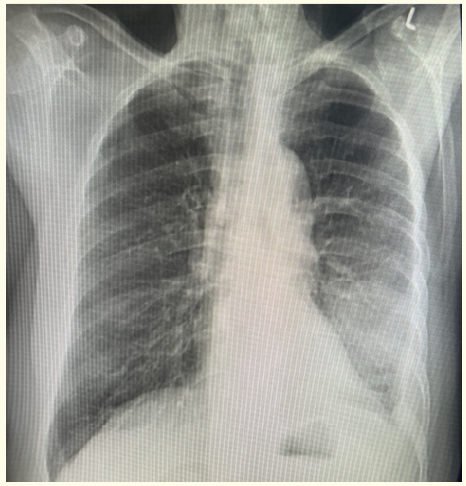

Diagnostic Performance of Chest Ultrasound in Diagnosing Pneumonia in Pediatric Patients at Mulago National Referral Hospital, Kampala, Uganda

Agnes Kyomuhangi, Daniel Atwine, Geoffrey Erem, Edison Arwanire Mworozi and Samuel Bugeza. 12(2): 03-16.